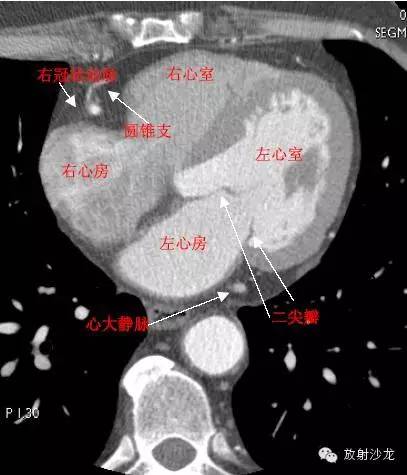

LA -Left Atrium左心房

RA -Right Atrium右心房

LV -Left Ventricle左心室

RV -Right Ventricle右心室

MitralValve二尖瓣

RCA -Right Coronary Artery 右冠状动脉

ConusBranch右动脉圆锥支

GCV–Great Cardiac Vein心大静脉